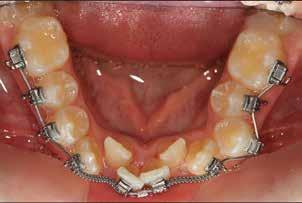

Ebben a cikkben egy 16 éves lánypáciens esetét szeretném bemutatni (1–7. képek)

A Pitts21-es fix készülékes kezelés során a harapásemelőket a felső nagyőrlő fogakra ragasztottuk, hogy a felső molárisok intrúziójával segítsék a harapás zárását (8. kép) Ún. keresztharapásos, majd később normál class 2-es gumihúzással (9–10. képek), továbbá az elülső fogakon alkalmazott ún. Rainbow harapás-záró gumihúzással (11. kép) korrigáltuk a jobb oldali teljes premolárisnyi distal-harapást, valamint az elülső nyitott harapást.

6 hónap után a nyitott harapás már nagyjából összezárásra került (12. kép)! A gumihordás a kezelés teljes hosszában folyamatos, éjjel-nappal, 22-24 órában az étkezések és az utánuk történő fogmosás kivételével.

A fix fogszabályozó készülék mindössze 16 hónapos kezelés után került eltávolításra! Páciensünk legnagyobb örömére állcsontműtét nélkül sikerült mind az arcesztétikai, mind a funkcionális rehabilitáció (13–18. képek)